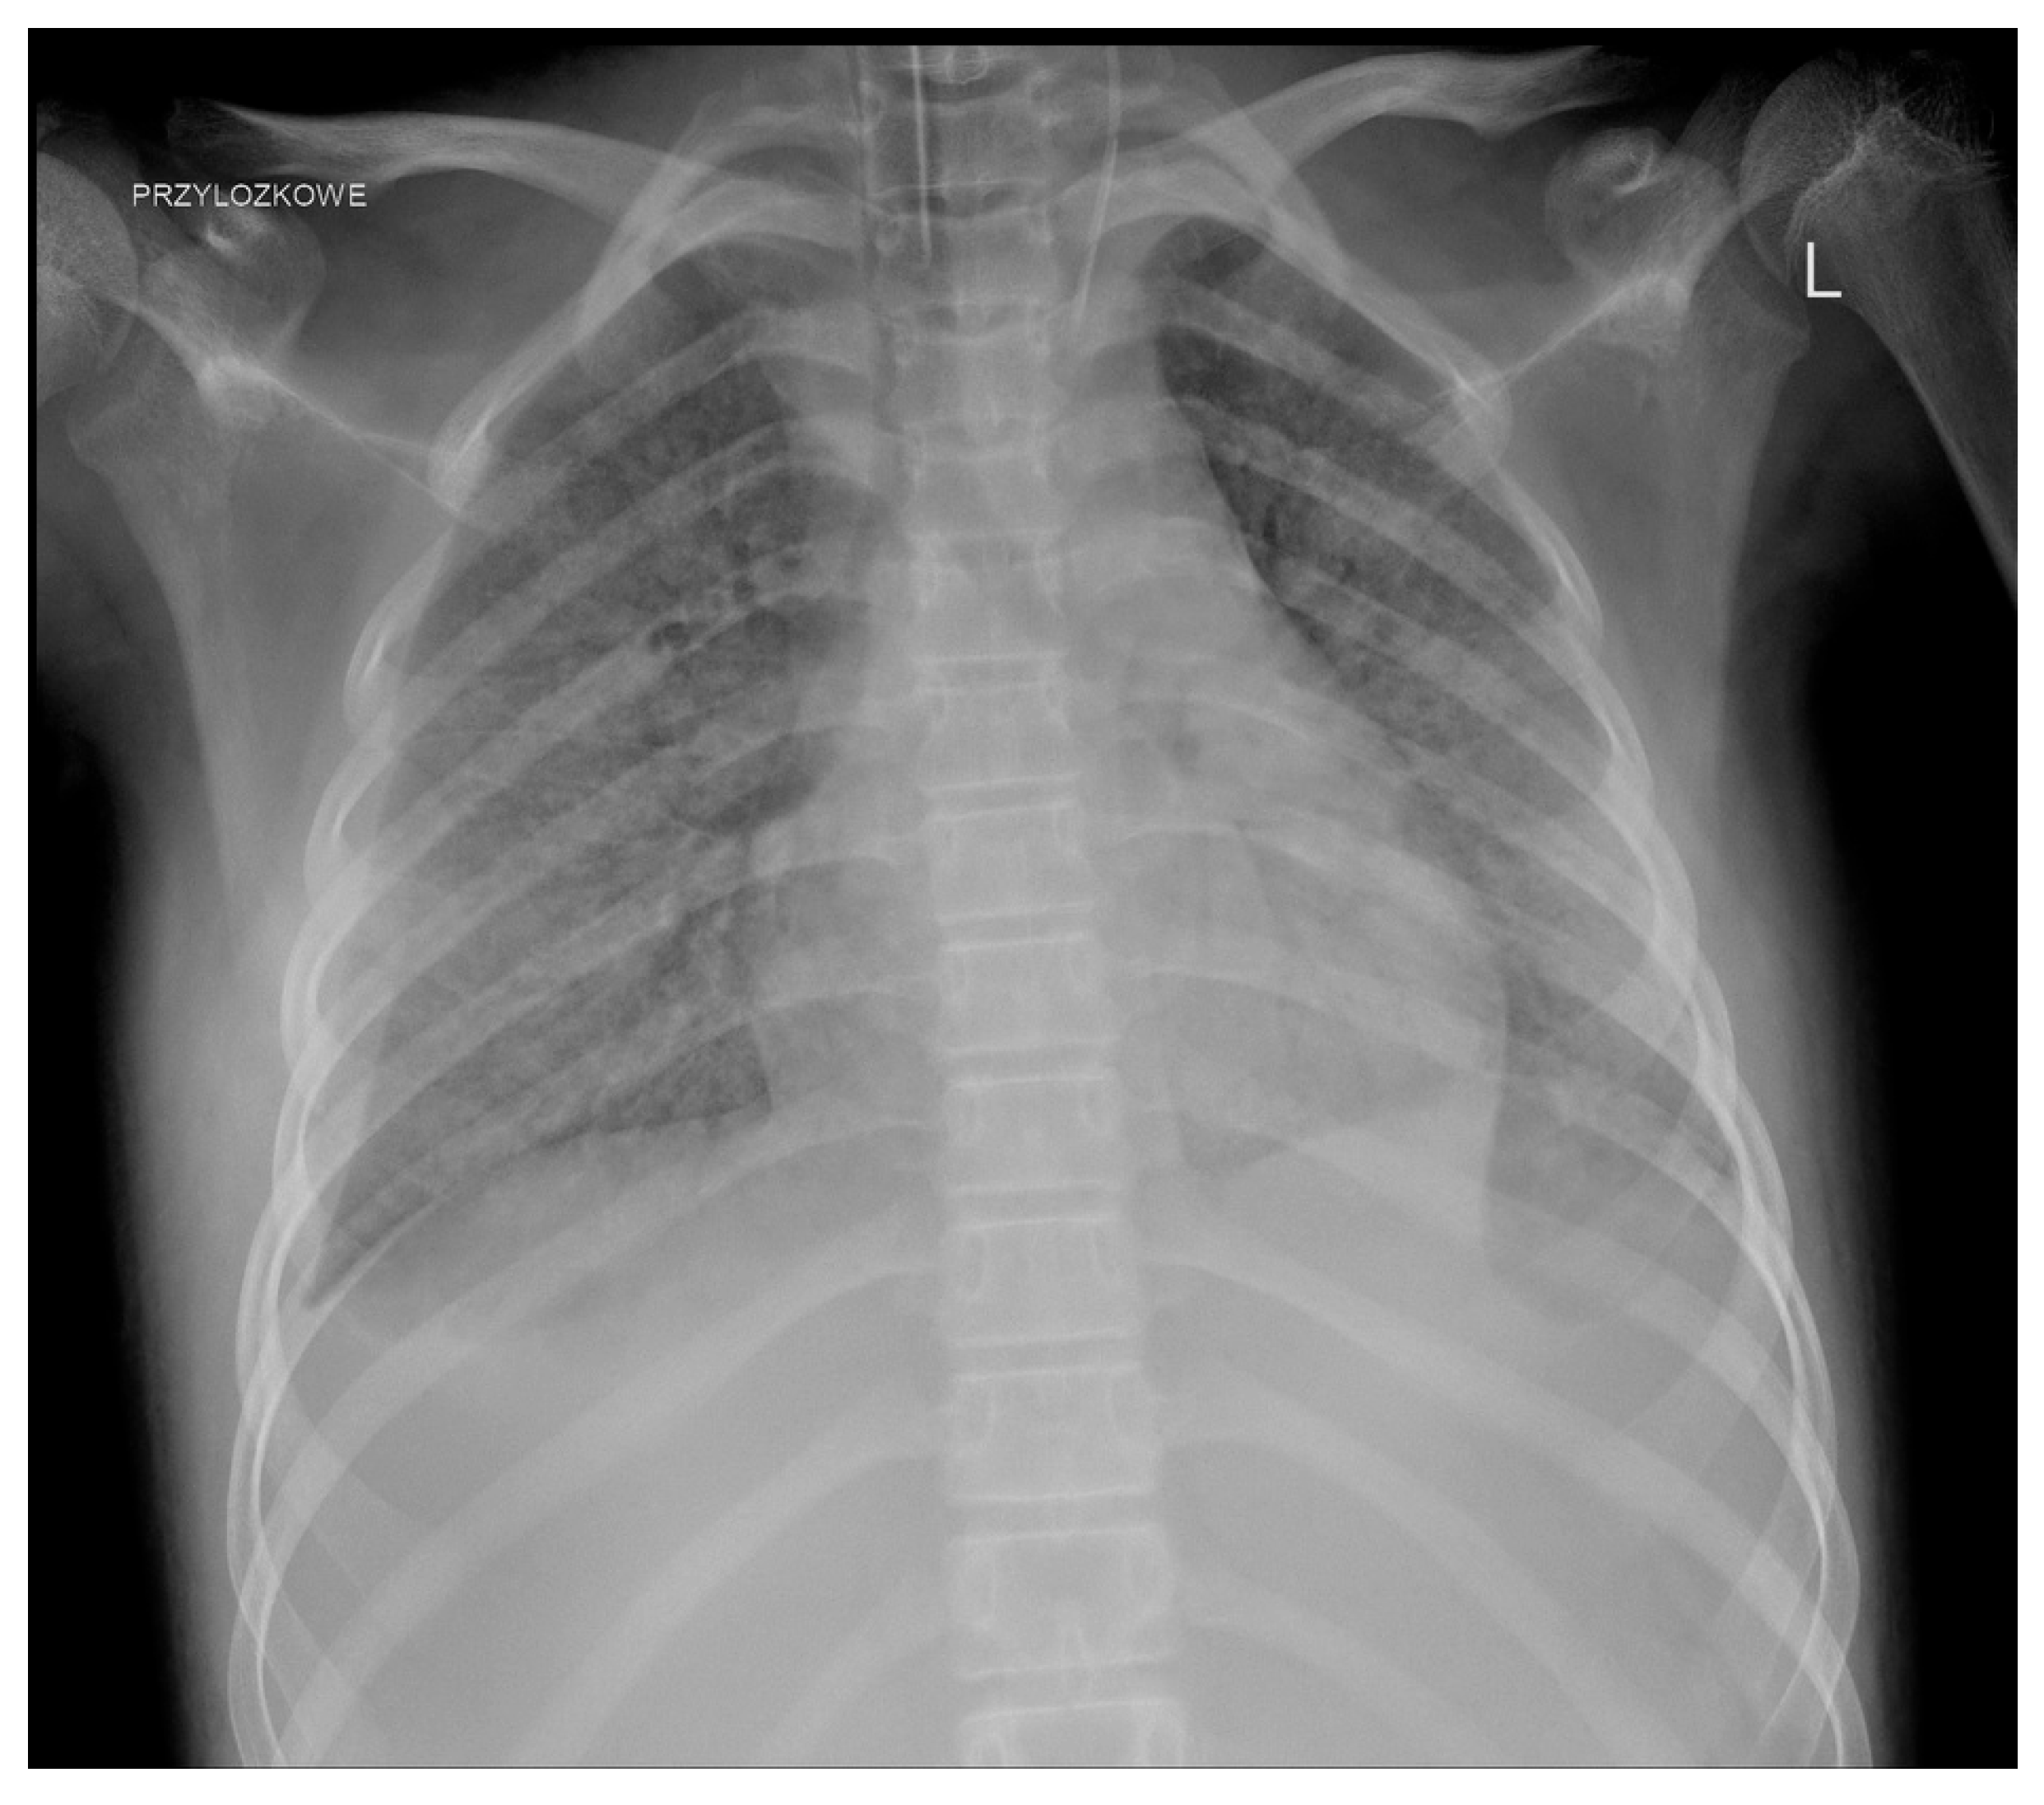

We observed a few complications related to GC administration. One patient developed an anaphylactic reaction during the second transfusion. One girl, who required hospitalisation in the ICU as a result of infection, about 2 h after the administration of the GC, developed shock symptoms with the deterioration of the general condition and circulatory and respiratory instability; transfusion-related acute lung injury (TRALI) was diagnosed after further investigation (Figure 3).

Figure 3. TRALI after GC transfusion.

A non-negligible issue is the side effects. Initially, side effects, mainly from the respiratory system, led to the suspension of GC use [6]. The significant development of serological methods has significantly improved the safety of GC use. The most common adverse reactions are not markedly different and do not occur more frequently than during the transfusion of other blood products [6]. Some of them can be avoided by proper donor screening, appropriate pretransfusion premedication (such as antihistamines, acetaminophen, and steroids), and maintaining adequate intervals between the administration of other medications (e.g., amphotericin B) [17]. Gea-Banacloche summarised the most common toxicities, including fever, HLA sensitisation, pulmonary reactions, and CMV infection (if CMV-positive donors are used) [10]. Fever appears to be the most common complication. Alloimmunisation seems particularly problematic in the context of further anticancer treatment (in one patient, we struggled for a long time with the consequences of this complication). The risk of transfusion-transmitted infection is low as donors are routinely screened for infectious diseases, but it still exists [9]. Pulmonary complications, which are considered acute transfusion-related adverse events, appear to cause particular (and justified) concerns. Grigull et al. reported the need for the temporary escalation of respiratory support in patients undergoing mechanical ventilation, worsening of pulmonary symptoms in two children with viral pneumonia, and even the development of progressive respiratory failure during GC transfusion [18]. In a systematic review covering studies from 1966 to 2006 on granulocyte transfusions in neutropenic children, the authors observed pulmonary complications in only seven recipients, ranging from mild to more severe respiratory symptoms, but TRALI was not reported. They concluded that novel methods of leukapheresis have significantly reduced the risk of severe pulmonary complications that were observed in the past [19]. However, such reports still appear even in significantly more recent studies. Díaz et al. in a group of 13 patients with underlying acute infection observed respiratory symptoms in 6 patients (46%) including hypoxemia and tachypnea that were likely secondary to GC transfusions [34]. Weingarten et al. described one episode of life-threatening grade 4 dyspnoea (in a cohort of 21 patients) [28]. TRALI, which was diagnosed in one of our patients, remained in close association with GC administration.